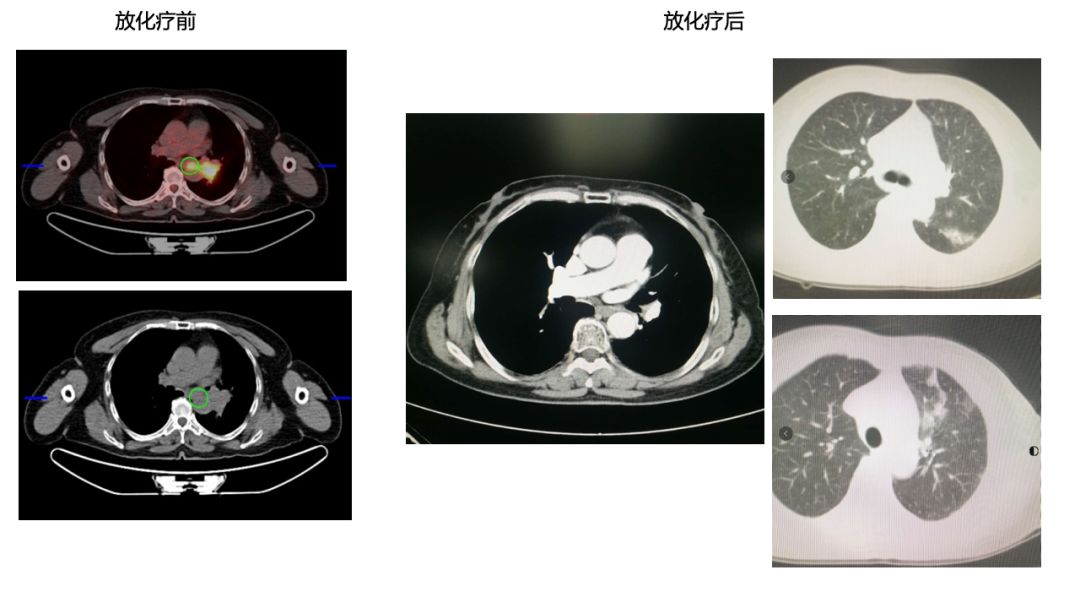

3)原发灶+8组LN(放疗区) PR 疗效。